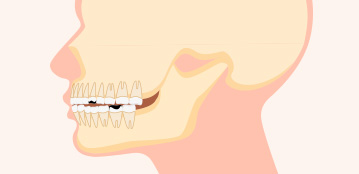

무턱 돌출

치아가 튀어나오고

동시에 무턱으로

돌출감이 더욱 심해진 경우